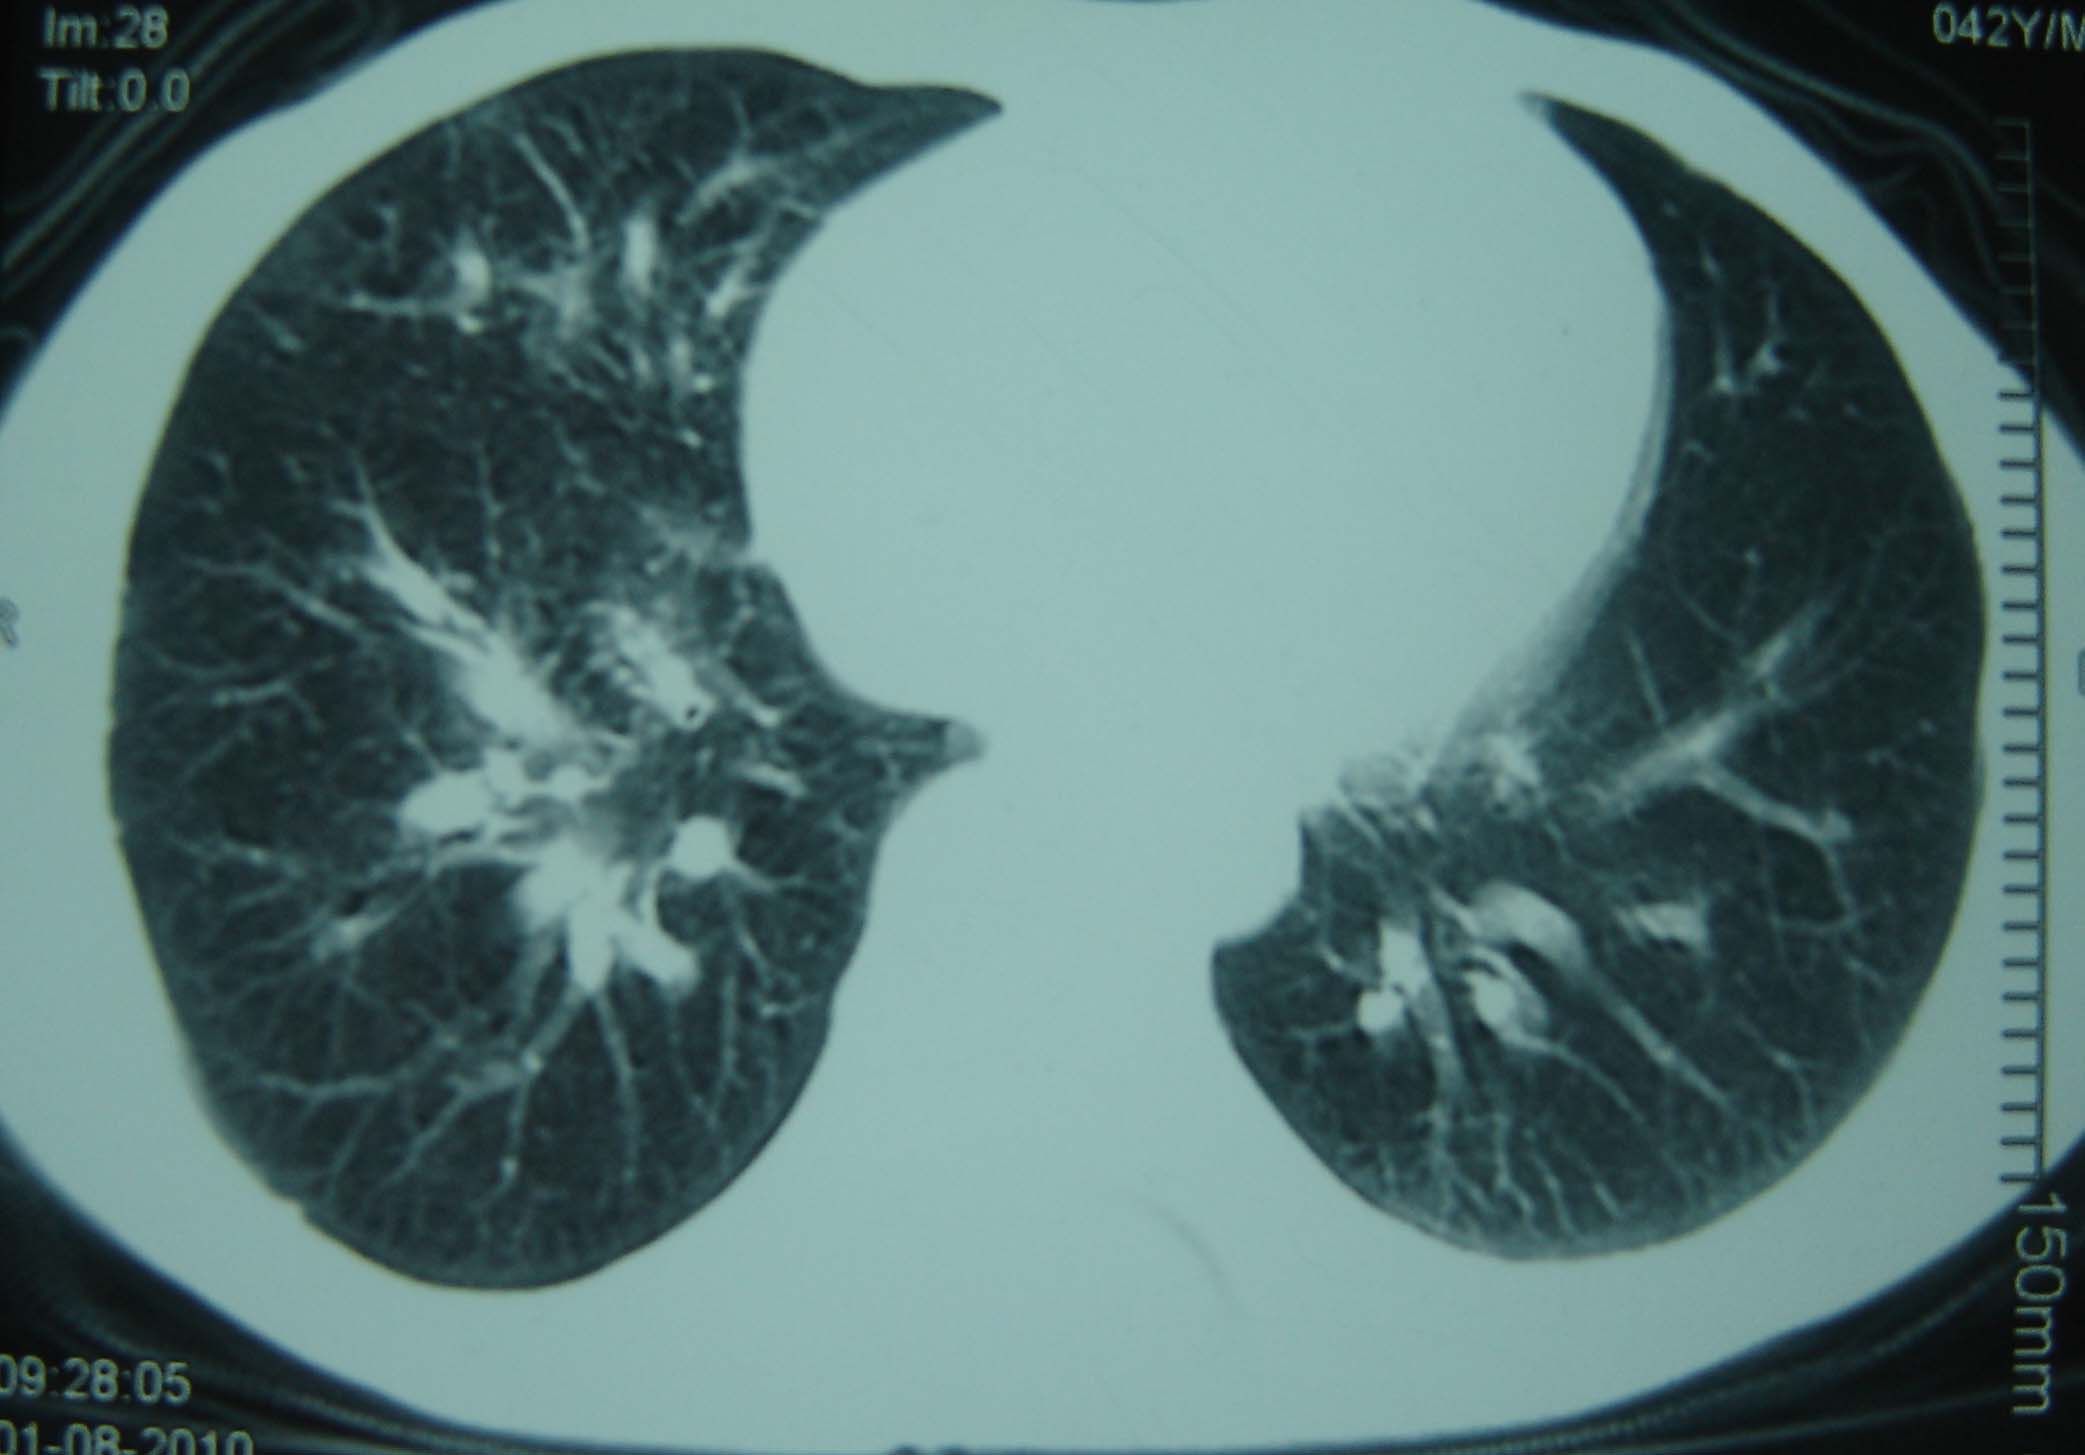

标题: CT25321:两肺多发结节 请会诊 [打印本页]

标题: CT25321:两肺多发结节 请会诊

男 、43岁,咳嗽胸痛,装修工,平时接触粉尘较多,有吸烟史10多年,纤维支气管镜检查未发现异常,胃镜、腹部b超检查亦未发现异常,颈部淋巴结活检未发现肿瘤细胞。

不能排除转移,如果不能找到原发灶,只有短期随访。

结节病?转移瘤?

结节病。

转移瘤?

1)考虑双肺及胸膜多发性转移瘤。2)肺气肿。

双肺结节病。